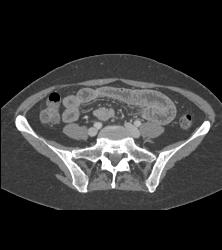

Carcinoid Tumor in Ileum